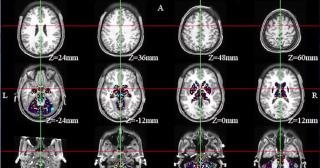

O femeie din Rusia a trăit 80 de ani cu un ac înfipt în creier. Părinţii ar fi încercat să o omoare la naştere

O femeie din Rusia a trăit 80 de ani cu un ac înfipt în creier. Părinţii ar fi încercat să o omoare la naştereO femeie din Rusia a trăit toată viaţa cu un ac de cusut înfipt în creier. Medicii din regiunea Sahalin au...